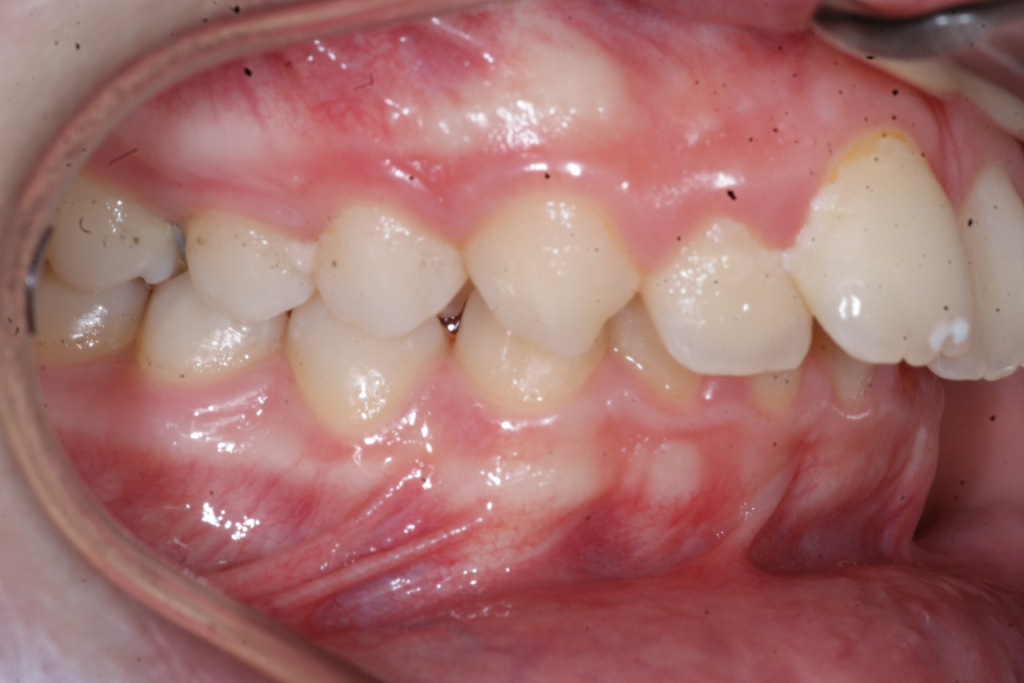

Correction d’une malocclusion de type Classe II.  Des appareils fixes (boîtiers) et une expansion palatine furent nécessaires pour améliorer ce sourire.  Traitement chez un adolescent, réalisé en 21 mois.